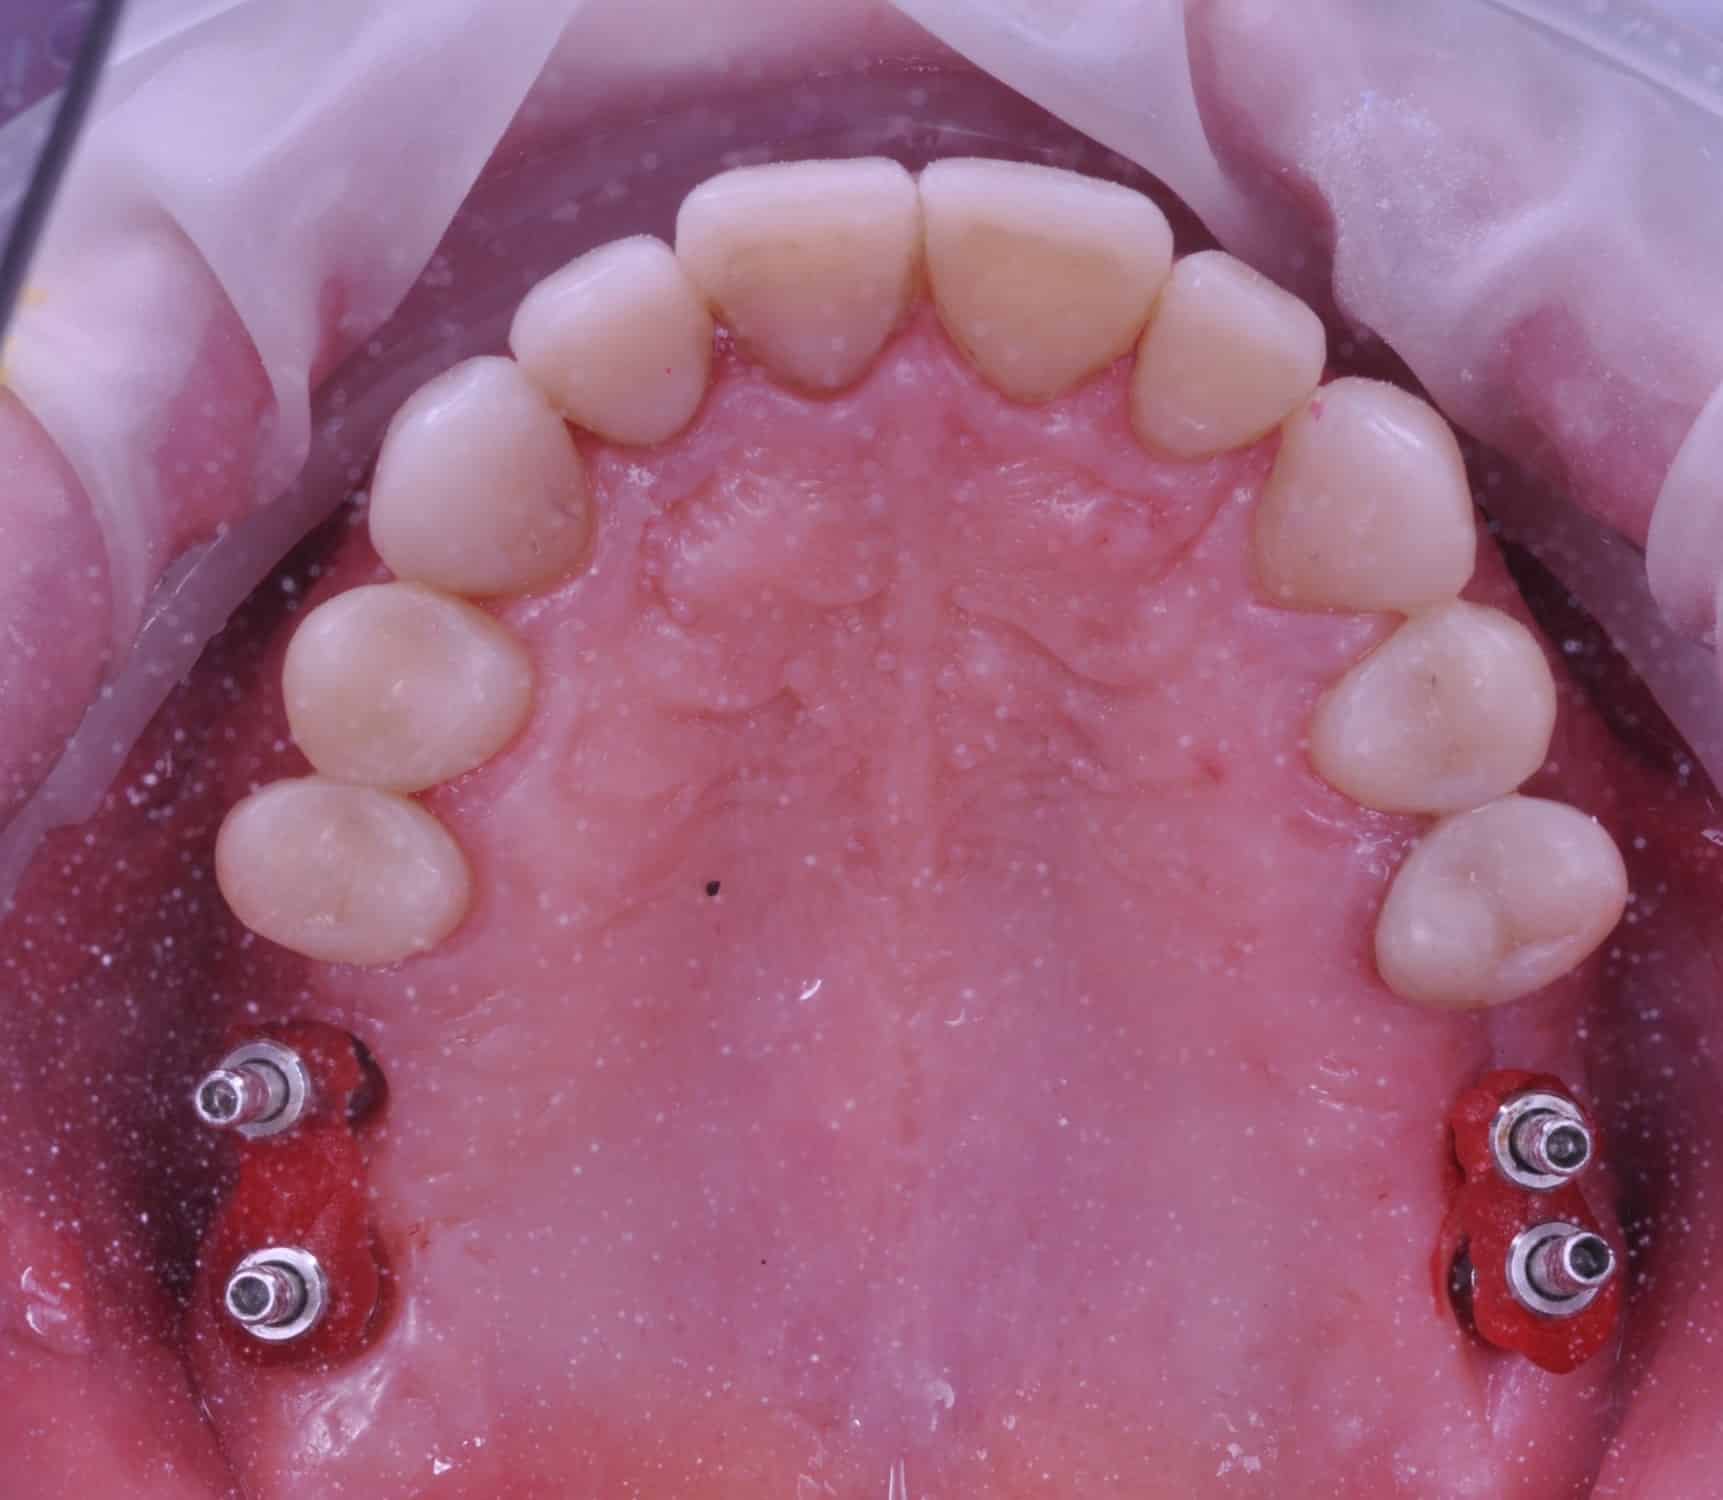

Împreună cu pacientul, am optat pentru inserarea implantelor cu ajutorul ghidului chirurgical pentru a plasa implantul în poziția protetică ideală și pentru a permite realizarea coroanelor insurubate pe implant. A fost efectuată scanarea digitală a arcadelor și a ocluziei pacientului, iar împreună cu tehnicianul radiolog de la DigiRay a fost suprapus fișierul .stl al amprentei digitale peste fișierul .dcm de la CBCT, utilizând software-ul 3Shape.

S-a planificat individual poziția și axul de inserție al fiecărui implant.

Avantajele realizării intervenției cu ajutorul ghidului chirurgical au fost:

Doar astfel putem crea profilul de emergență corect al coroanei dentare, ceea ce permite conformarea papilei și a sulcusului.